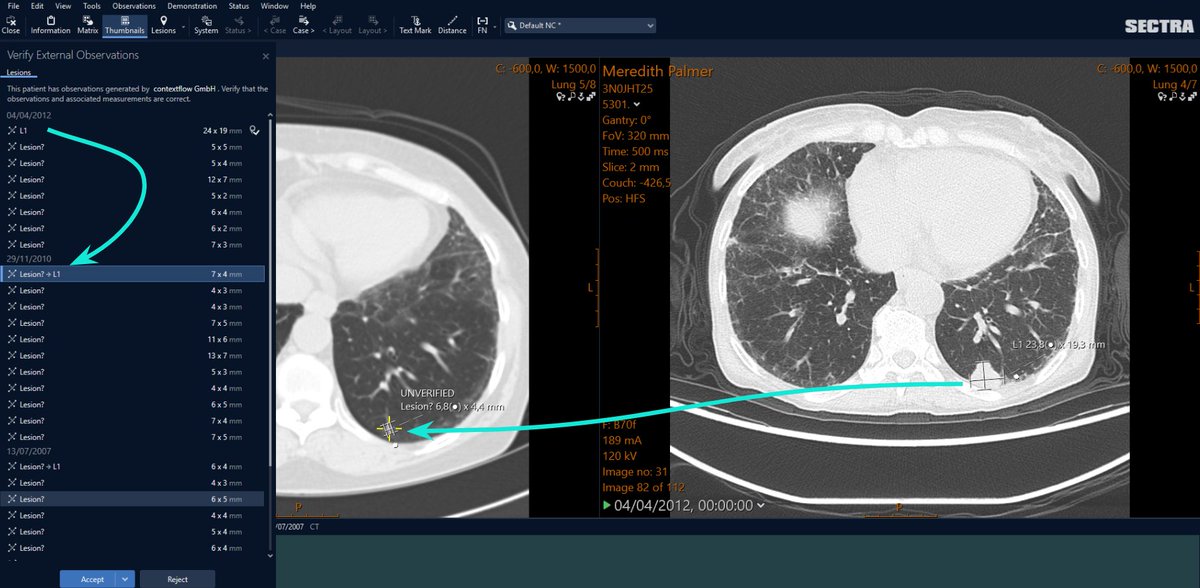

🫁 Research from Zurich compared two methods for measuring #emphysema in CT scans of #COPD patients: traditional HU vs. @contextflow_rad's #deeplearning method